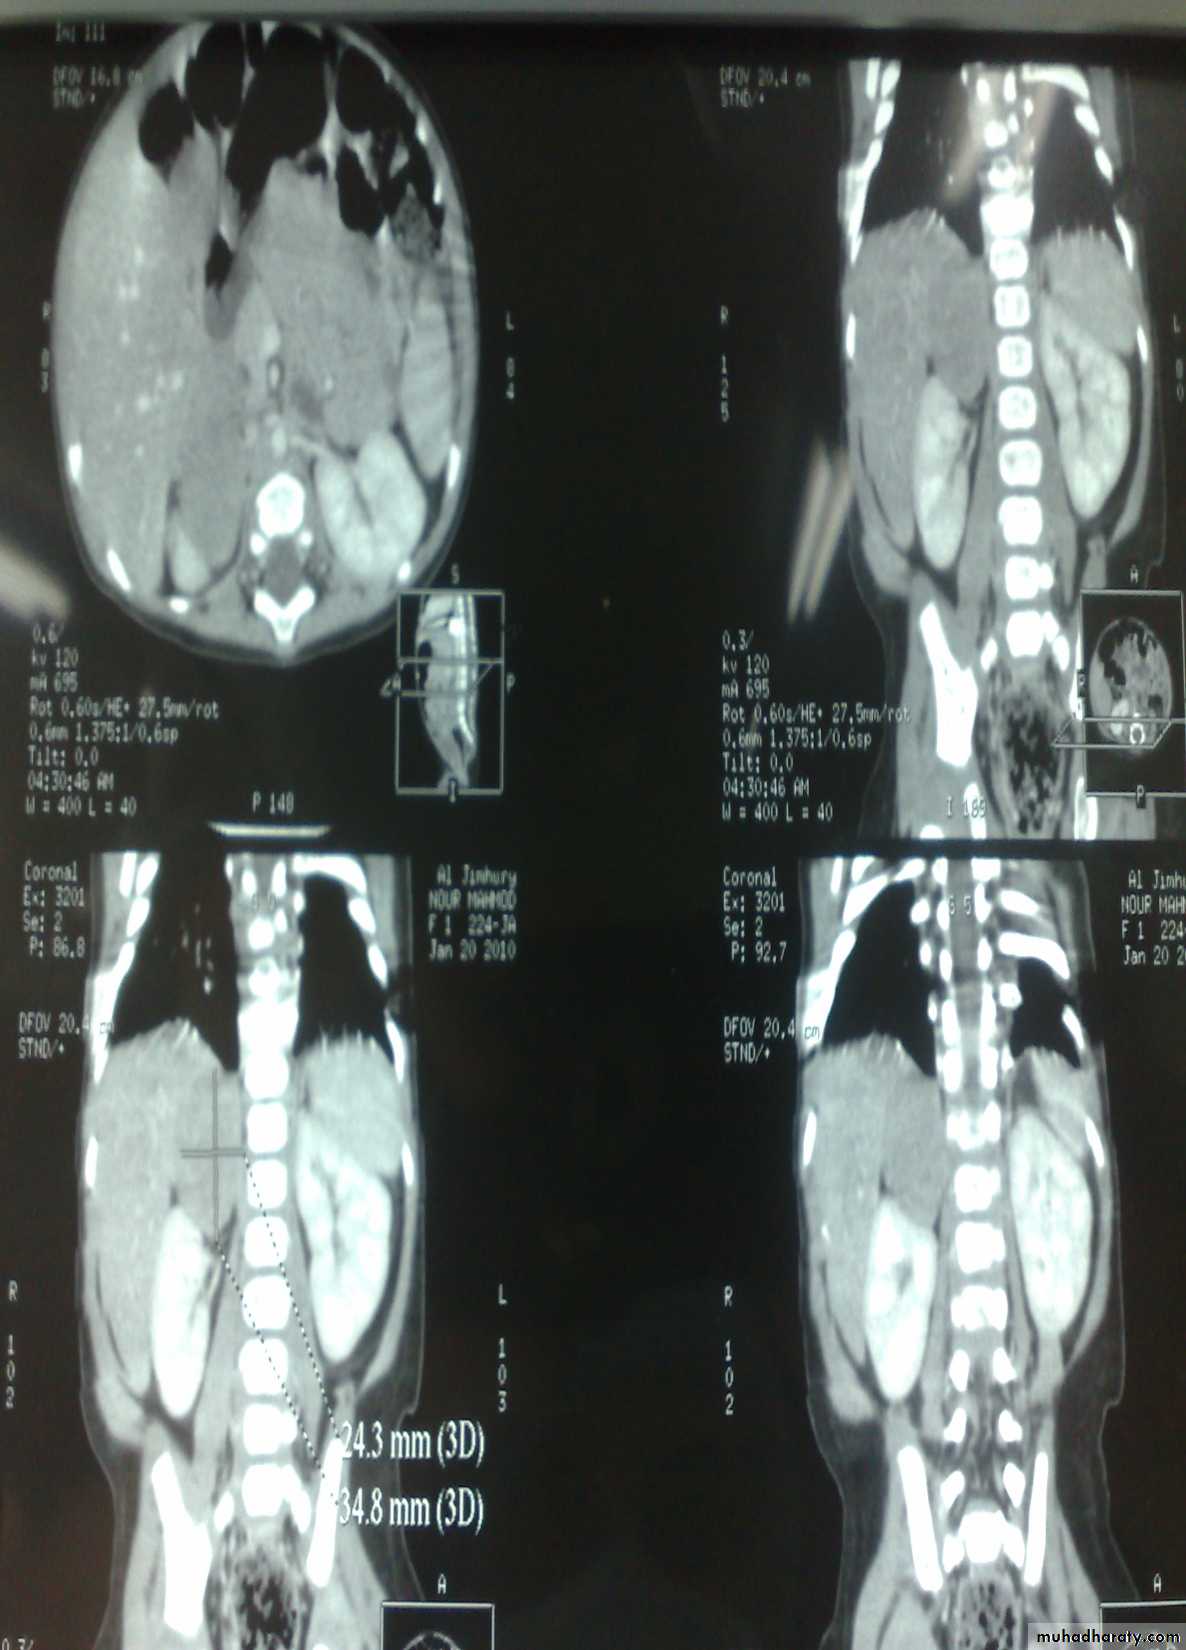

The Child with an Abdominal Mass5 years child, presented with mass in the flank.

DDx of mass in the flank:1- Wilms tumor

2- Neuroblastoma

3- Neglected PUJ obstruction

Presentation:

1- Mass2- hematuria

3- hypertension

Treatment by surgery remove the kidney + chemotherapy

Neuroblastoma in the adrenal gland